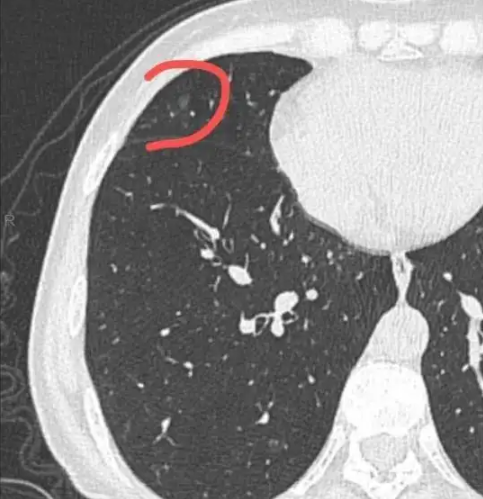

情况描述:2021/01/29初次体检时,发现左肺上叶磨玻璃结节为7mm。医生告诉我,肺结节没有特效药,只能通过手术切除。但现在我还没有达到手术适应症,所以我被要求每三个月随访一次,以防止结节发生恶变。我在网上查过。许多人说肺结节处于肺癌的早期阶段。磨玻璃结节恶变的比例更大。手术会影响肺功能,复发率仍然很高。我真的不知道该怎么办。总不能干等手术吧?请各位帮帮我!